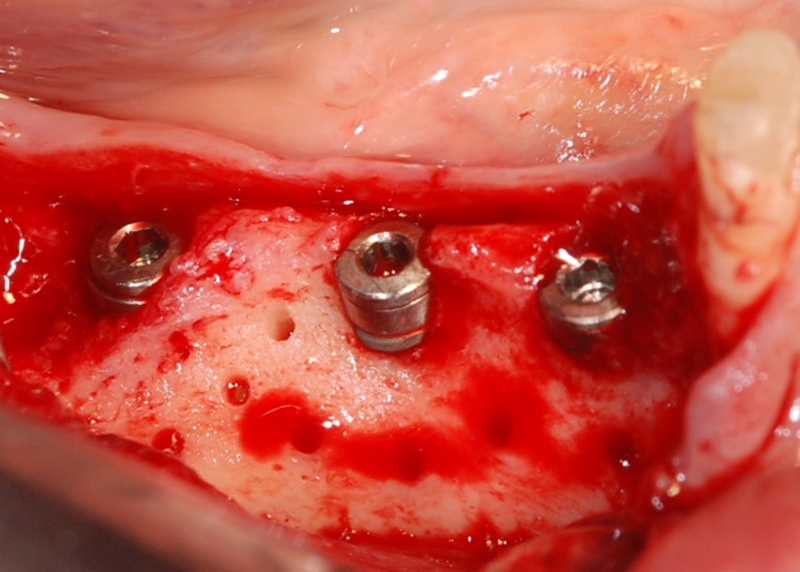

botiss cerabone® & Jason® membrane for horizontal augmentation - Clinical case by Dr. M. Steigmann

Three implants placed in a narrow posterior mandible